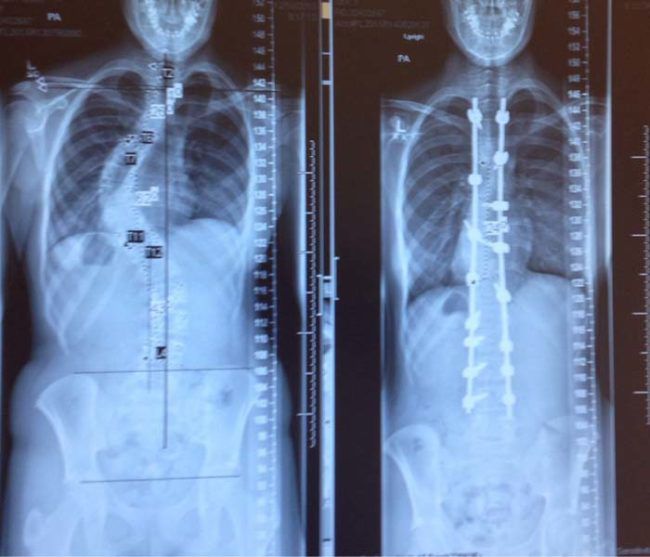

/ 8Skolioza

Można powiedzieć, że "przed" i "po". Swoją drogą, chirurdzy są niesamowici. Szacunek.